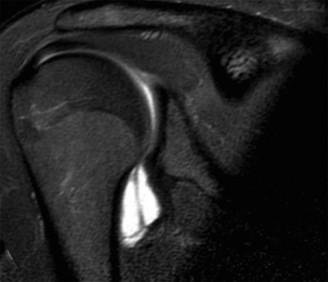

Identify the muscles that compose the force couples in the transverse and coronal planes? CASE 3 A 35-year-old male has had left shoulder pain for 4 months, ever since a low-speed motor vehicle accident (MVA). Physical examination demonstrates preserved range of motion but pain and some weakness with Jobe’s testing. His imaging is shown in Figure 2–8.

Figure 2–8_Reproduced with permission from Stadnick ME. _Partial Rotator Cuff Tears. MRI Web Clinic. 2007 (Apr).

What is the most likely diagnosis?

The correct answer is (A). These are best diagnosed on an MRI as seen in the imaging provided; addition of intra-articular contrast can further improve this study. Answer B, full-thickness rotator cuff tear, is incorrect as the bursal side of the tendon can be seen to be in continuity. Answer C, a SLAP lesion, will be visualized as a labral tear on a coronal MRI and will be found at the biceps root. Answer D, an ALPSA lesion, will be most clearly seen on an axial MRI. It is a variant of a Bankart lesion where the labrum is displaced medially and inferiorly rolling down the glenoid neck underneath the periosteum.

MRI remains the most popular imaging modality for diagnosing rotator cuff tears. Normal rotator cuff tendon appears dark on both T1 and T2 sequences. Tears may be noted as being full-thickness, articular-sided, bursal-sided, or intrasubstance. They are visualized as a disruption in the regular contour of the tendon and increased signal intensity on T2 sequences. Occasionally, an MR arthrogram may provide additional information regarding a cuff tear, although this is not routinely ordered.